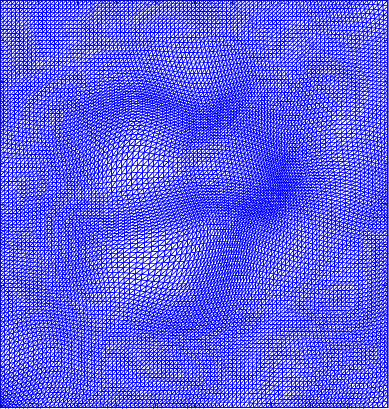

Figure 5 shows the ground truth and recovered maps of the registration maps in the last row of Table 4. It can be seen that ground truth low-rank mapping shown in Figure 5(a) resembles the recovered low-rank mapping shown in Figure 5(c). This again shows that we could obtain a meaningful mapping from the decomposition.

Figure 6 displays the 4 mappings as in Example 3 and 4. Again, we can see that after the decomposition of the Beltrami descriptor, the decpmposed mappings to large extent resemble the corresponding ones.